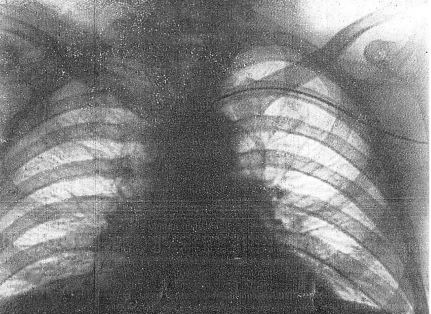

世界初の血管造影の報告である.造影剤としては,原子番号の大きな元素をいろいろ試した結果,臭化ストロンチウム(SrBr2)を使用している.ストロンチウムは当時,くる病,低カルシウム血症の治療に使われていたらしい.これをヒトの上肢に,中枢側の血流を(おそらく駆血帯により)うっ滞させた状態で動注あるいは静注し,得られた写真にはそれなりに動静脈が写っている.しかし結局この試みは臨床応用に発展することなく,単発に終わってしまった.論文の最後で,著者らも油性造影剤(リピオドール)を使う方向に転換したことを述べているが,何はともあれ世界初の血管造影であった.